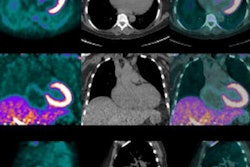

When faced with a gastrointestinal or genitourinary imaging emergency, adding SPECT/CT to the standard imaging options can help identify the source of the problem and lead to an appropriate intervention, according to this study."Traditional nuclear medicine studies, such as bleeding and hepatobiliary scans, make use of dynamic and planar images to come to a diagnosis," explained Dr. Elham Safaie from Stony Book University. "Sometimes these types of imaging modalities are not sufficient at arriving to a final conclusion. The use of SPECT/CT has superior spatial resolution and accurate localization with the use of the CT component. This would lead to a definite diagnosis in complex cases and will lead to better patient management as a result."

In this retrospective study, Safaie and colleagues reviewed 23 consecutive abdominal emergency studies in which patients underwent initial dynamic imaging followed by SPECT/CT between July 2013 and March 2016. Because all standard dynamic studies were inconclusive, SPECT/CT was performed as a follow-up.

SPECT/CT accurately identified the regional anatomy and source of gastrointestinal bleeding in all six cases, which involved two large bowels and four small bowels. In one case, the patient had both small bowel and peritoneal bleeding at surgery.

In addition, among 14 hepatobiliary studies, SPECT/CT localized nine biliary leaks, confirmed biliary atresia in three patients, and excluded cholecystitis for two people. All of this was accomplished with an average added scan time of 20 to 30 minutes.